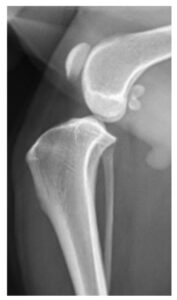

症例1. TPLOを実施した症例(7歳、ビーグル、9 kg)

| 治療前(側方像) | 治療後(側方像) | 治療前(前後像) | 治療後(前後像) |